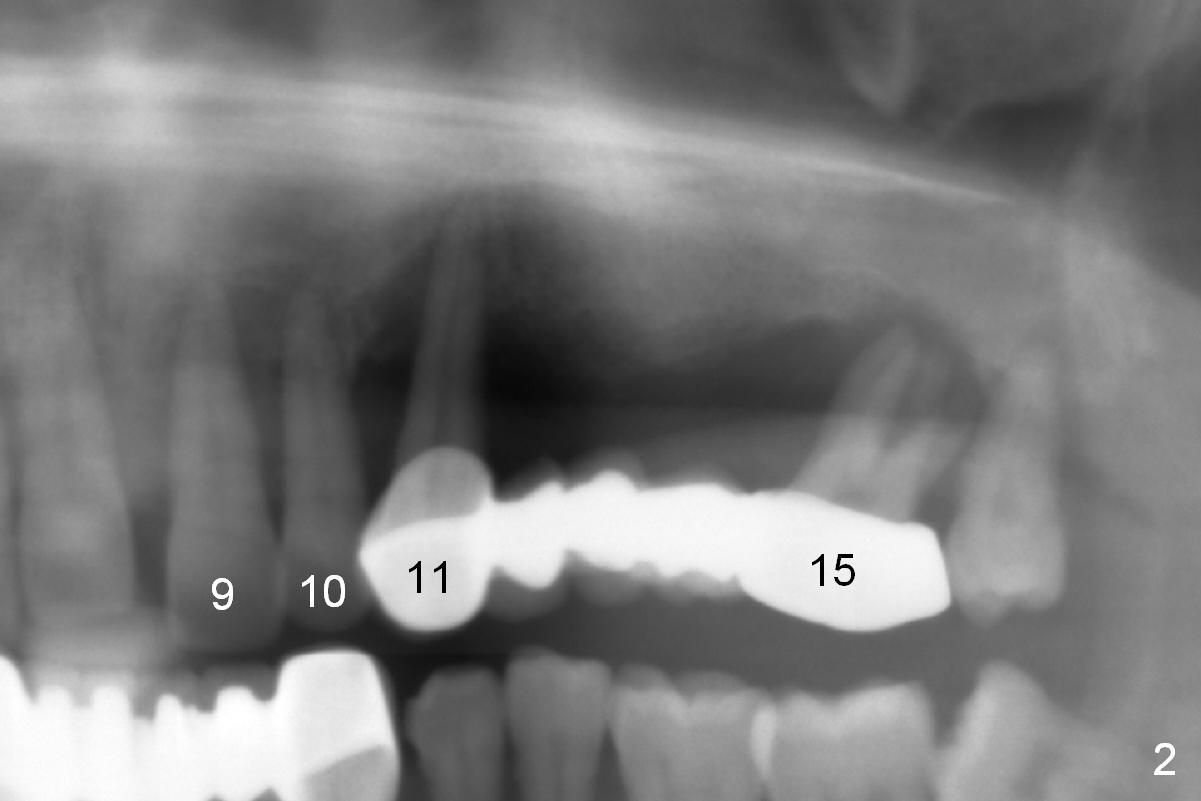

A 45-year-old man has advanced periodontitis and bruxism (sufficient remaining bone height, Fig.1). Full mouth restoration will be done by quadrant with preservation of a few of relatively healthy teeth. The 1st quadrant to be treated will be the upper left (Fig.2). The teeth #9-11 and 15 will be extracted (Metronidazole) with immediate implants. A delayed implant will be added at #13 for #11-15 bridge (Fig.4). In addition to the large radiolucency around the roots of #9 and 10 (Fig.3 red dashed line), the gingiva at #11 and 15 is excessively thick (red arrows). For example at #11, a long implant has to be placed a little more outside the bone (Fig.4 green area), since the longest cuff of the abutment (red area) is 5 mm for UF implant system. The longer the cuff, the less amount of the implant will be outside the bone with less chance of periimplantitis. When the coronal implant threads are exposed, a large amount of bone graft has to be placed (Fig.4 yellow circles).